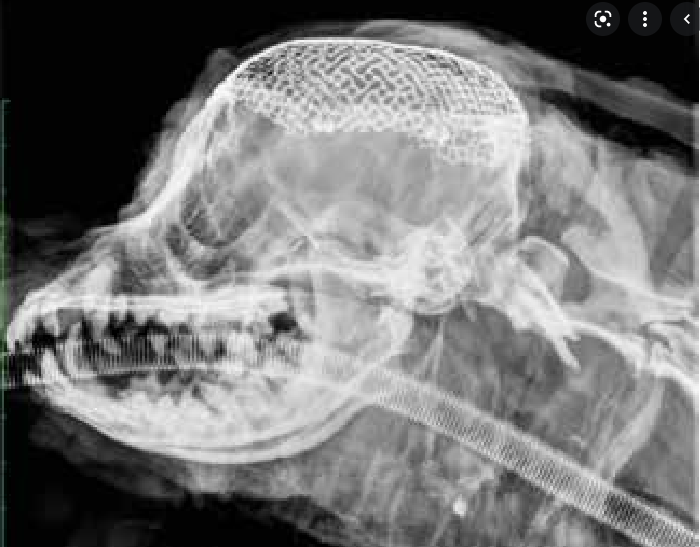

개두술 후 금속 매쉬를 이용한 두개골 봉합 자료, 반려견

무엇을 상상하든 그 이상의 결과물을 만들정도로 최근 의료 기술은 너무도 잘 발달하고 있음.

안되는것보다는 안하는것이거나 못하는것이 대부분인 시대인듯 하다.